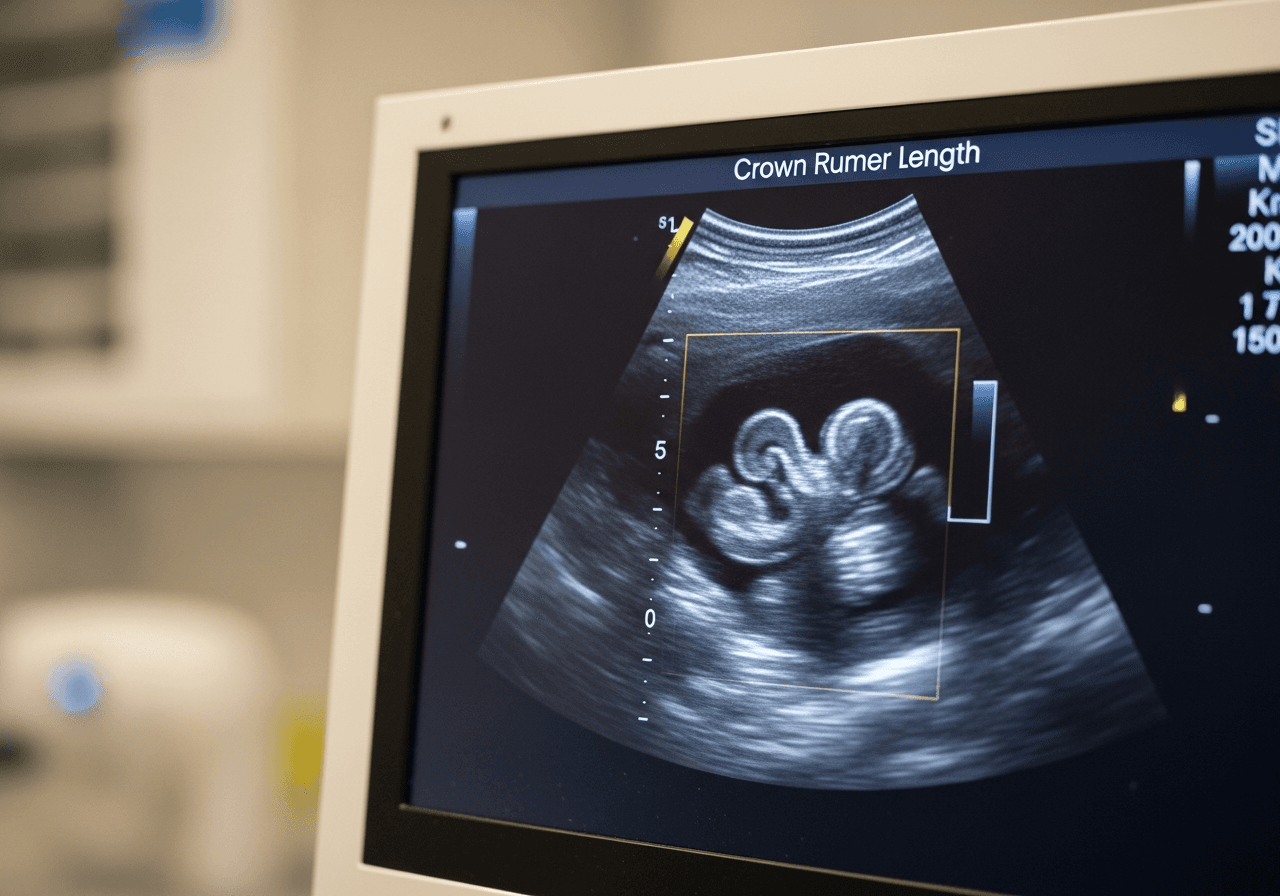

Longueur cranio-caudale (LCC)

La mesure de référence au 1er trimestre